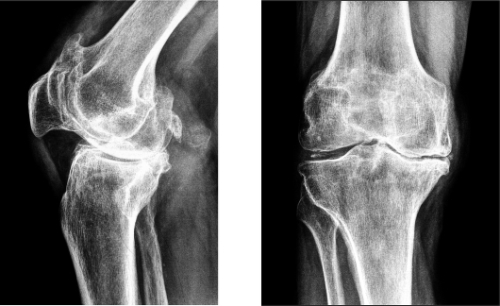

При развитии, на третьей стадии, боли уже имеют постоянный характер и достаточно сильные независимо от того человек двигается или нет. Также они усиливаются «на погоду». Из-за тог что колено ограничивается в подвижности, меняется походка человека, сустав становится больше по размерам и теряет свою форму. Это приводит к развитию частых воспалительных процессов и перенапряжению окружающих мышц. На этой стадии человек обычно и отправляется к врачу.